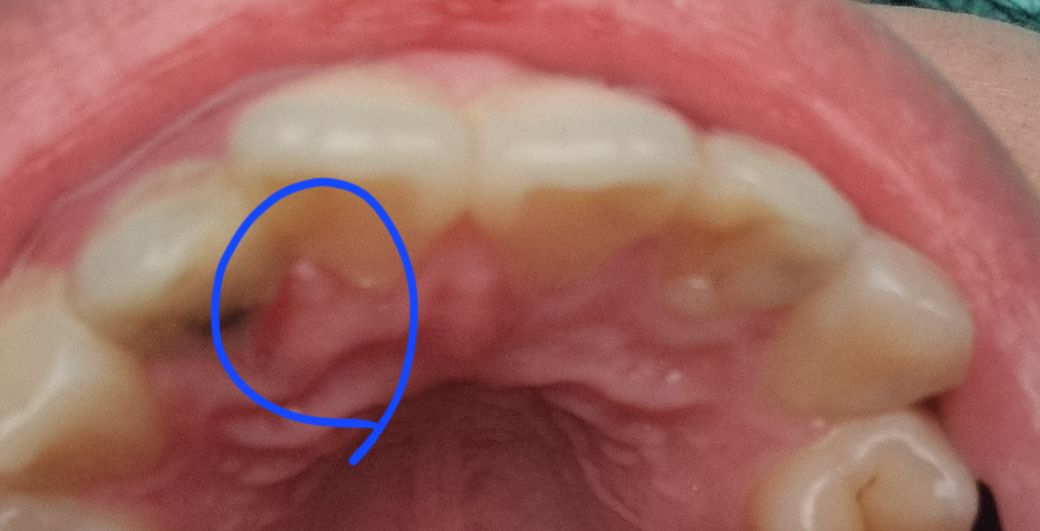

말 그대로 앞니 뒤의 잇몸이 부었습니다. 혀로 건드리면 아프고 많이 부은 건지 가만히 있어도 신경 쓰이네요... 앞니에 충치가 있다고 하시긴 했는데 신경치료를 당장해야 할 정도로 심각하진 않다고 하셨었습니다 단순 구내염일까요?

• 1번 째 사진

사진 상에서는 특별히 문제가 보이지는 않습니다. 단순히 부은 것이라면 일시적일 가능성이 높습니다.

구내염은 아니고 단순 치아사이의 잇몸(치간 잇몸)에 염증이 생긴 것으로 보입니다. 며칠 지나면 저절로 없어집니다. 없어진 후에는 치과에 가서 그 부위 포함해서 전체적인 스켈링 받는 것을 권합니다.

1. 해당 부위는 절치유두부위로 위생관리가 부족하면 염증이 생겨 붓고 아플 수 있습니다.

2. 치과에서 스케일링 받고, 항생제 연고 넣어두면 가라앉을 것 같습니다.

3. 충치가 치아뿌리쪽으로 있어서 잇몸쪽에 가까워 영향을 주었을 수도 있습니다. 정지우식이 아니라면 신경치료는 아닐지라도 충치치료는 하면 좋을 것 같습니다.